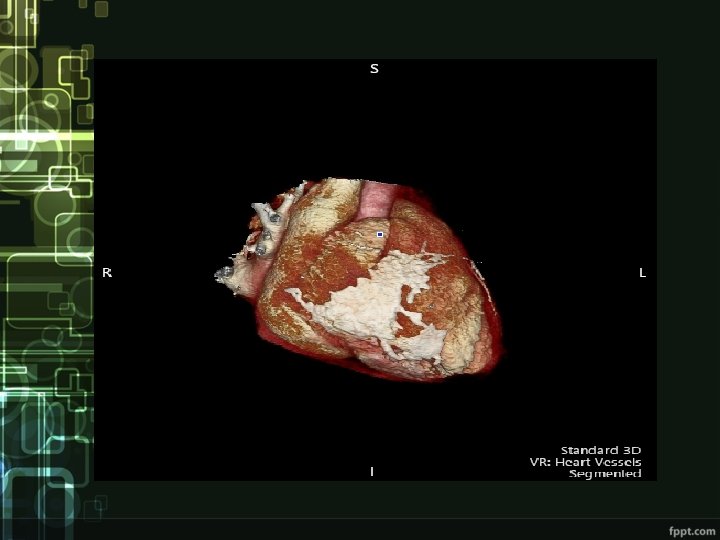

Diagnostics • Clinical picture • ECG – low voltage, repolarization changes (inverted T waves) • ECHO – thickened pericardium, impaired ventricular filling, „dancing septum“, IVC and atrial dilatation • Other imaging techniques

Treatment • pericardiectomy